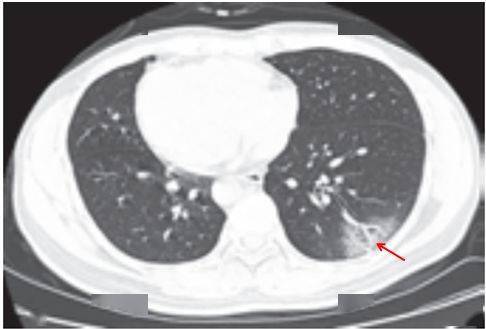

(一)病灶分布

病灶以 肺外围背侧为主,以两肺下叶为著,与胸膜常紧贴,提示新冠肺炎病变多首先侵犯皮层肺组织的细支气管及肺泡上皮, 病灶分布逐步从外周向中央扩展(图 2-1)

图2-1 早期病灶多数分布贴近胸膜( 共4张 )